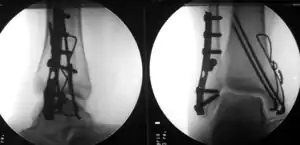

Surgically fixated bimalleolar ankle fracture

The broad goals of treating ankle fractures are restoring the ankle joint to normal alignment, healing the fracture, and preventing arthritis.[8] The stability of the ankle joint often dictates treatment. Certain fracture patterns are stable and are thus treated without surgery similarly to ankle sprains. Unstable fractures require surgery, most often an open reduction and internal fixation (ORIF), which is usually performed with permanently implanted metal hardware that holds the bones in place while the natural healing process occurs. A cast or splint will be required to immobilize the ankle following surgery.[11] Stable ankle fractures with preserved joint alignment may be treated with non-operative measures (splinting, casting, and/or walking boot).[11]